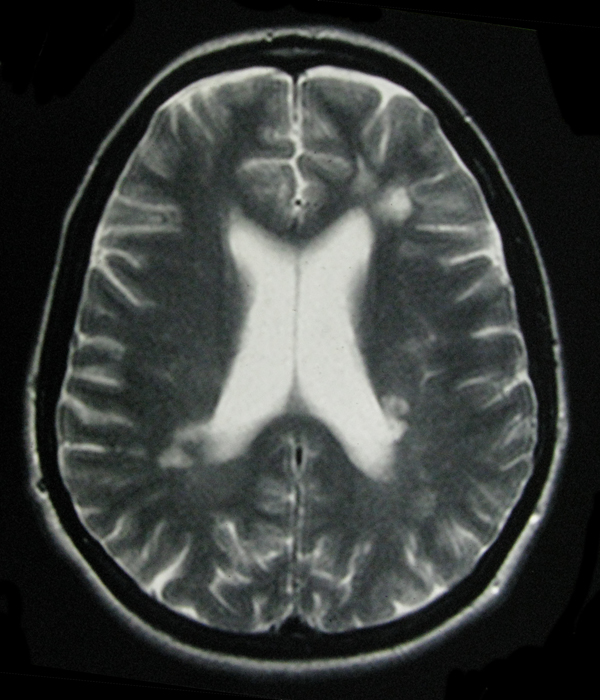

- My Brain in 2009